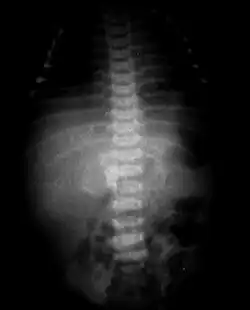

Il est possible que certains cas répertoriés soient en fait des tératomes. A la différence des fœtus in fœtu, les tératomes ont un potentiel de croissance indépendant et peuvent dégénérer en tumeur maligne. Un bon moyen de différencier ces deux entités est la présence d'une colonne vertébrale, habituellement absente dans les tératomes[3].